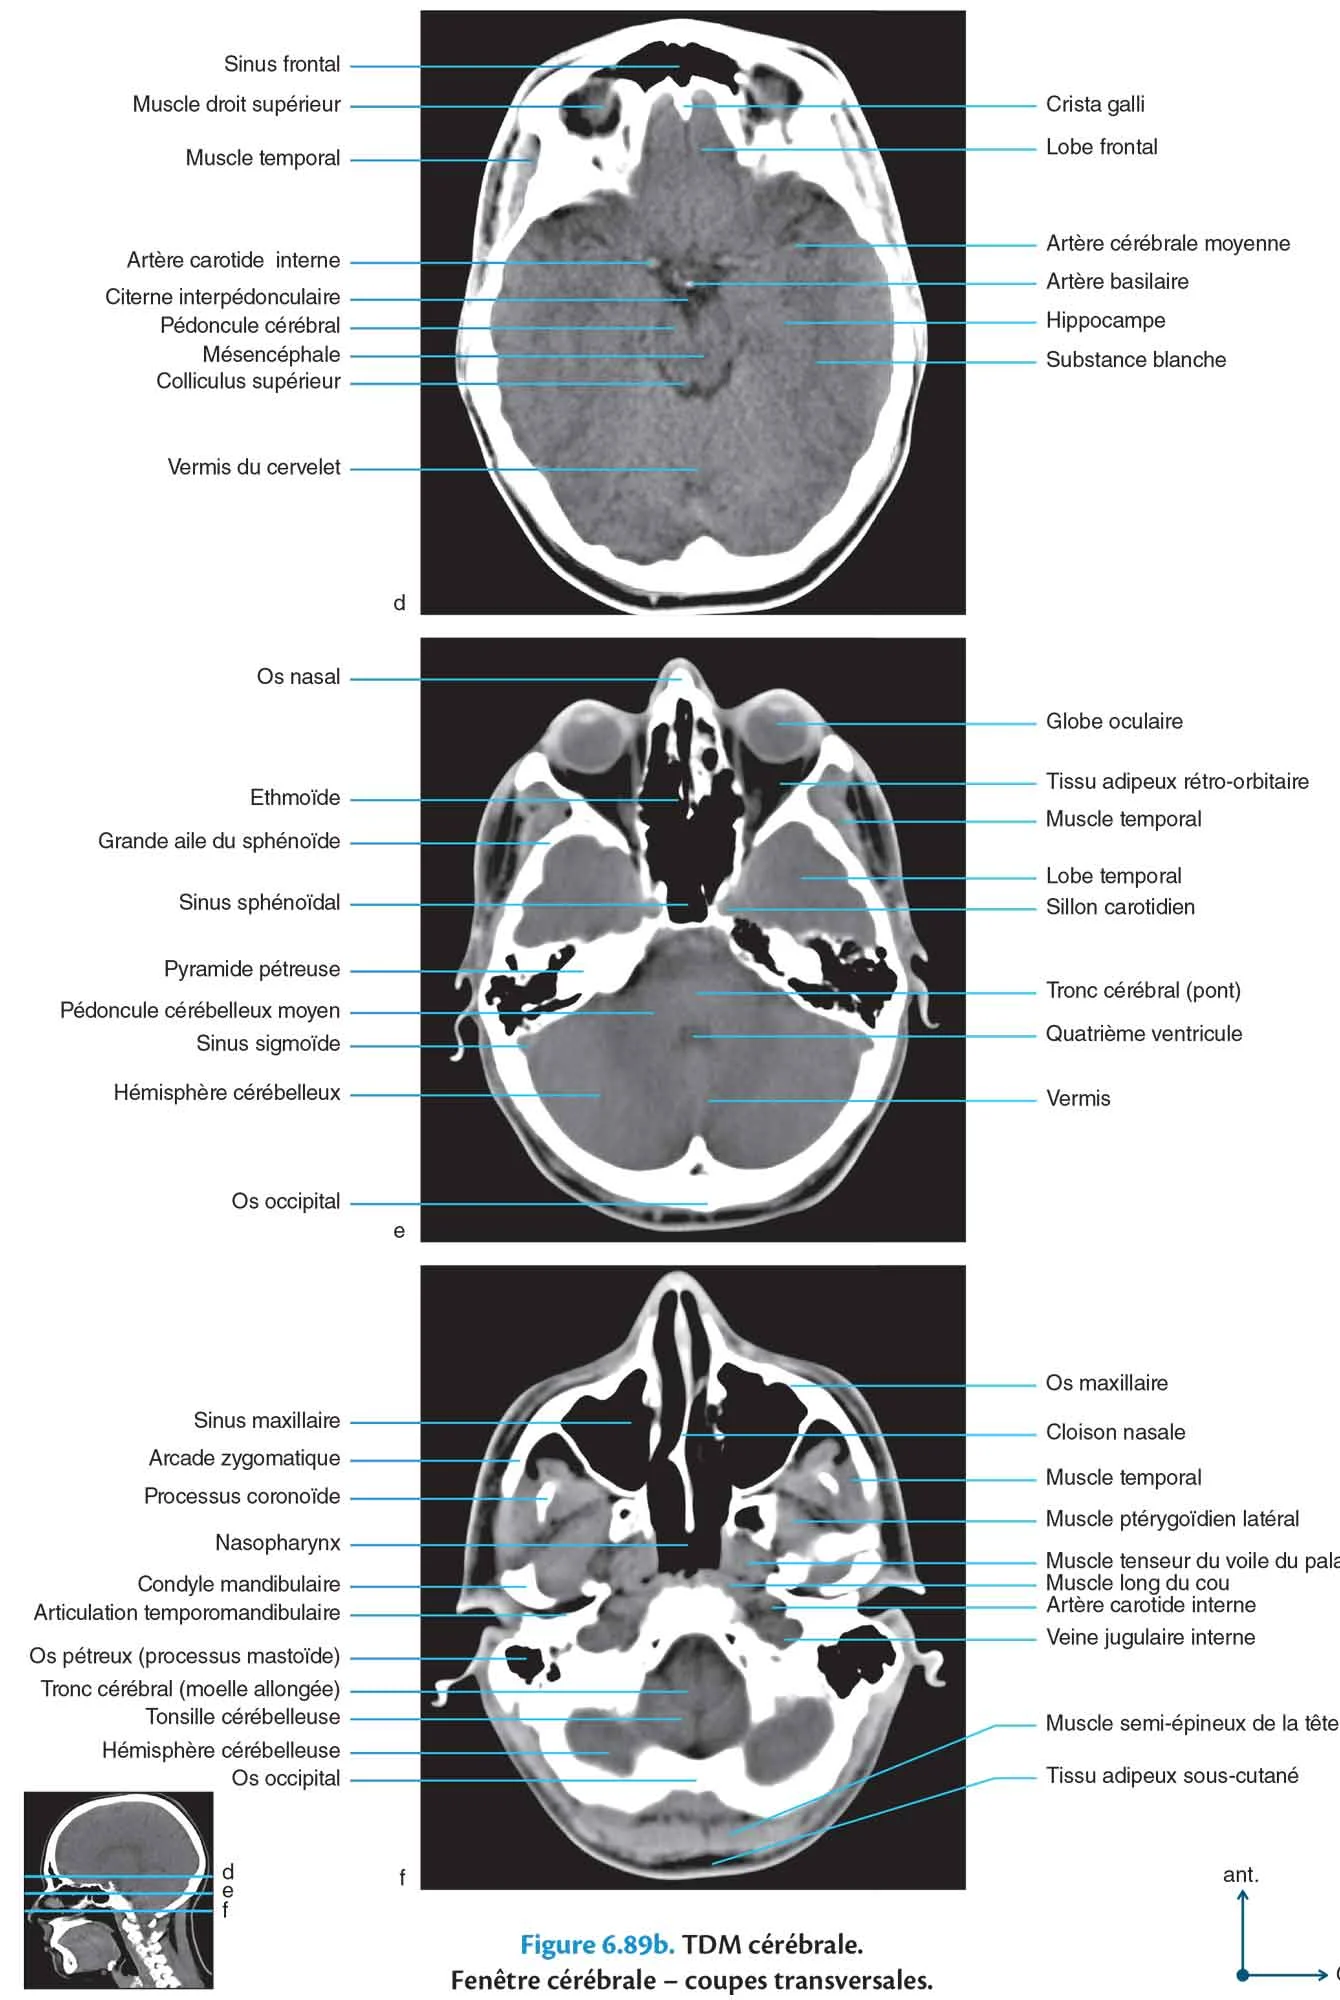

TDM cérébrale

Fig 6.89b